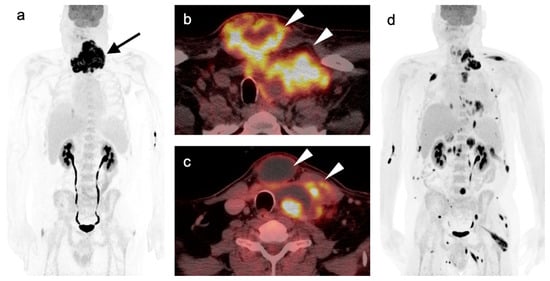

2.2. Squamous Cell Carcinoma of the Head and Neck (SCCHN)

2.3. Nasopharyngeal Carcinoma

2.6. Thyroid Cancer

- Differentiated thyroid cancer